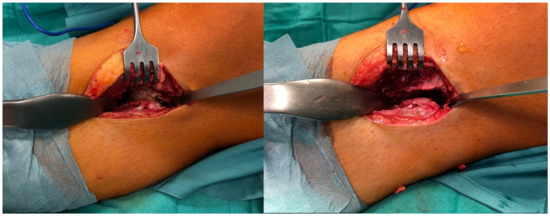

The MRI scan without contrast showed no thickened cartilaginous cap (Figure 3).

Figure 3. MRI scan in horizontal view showing the synostosis of the right side.